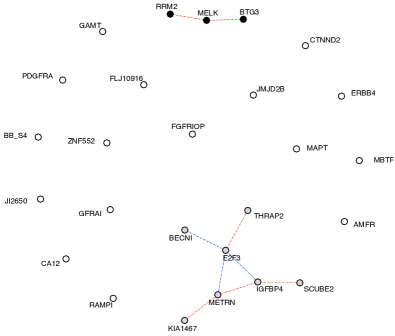

Figure 3 plots the resulting networks obtained for three different penalizations. The penalization parameters were heuristically chosen from the number of expected nonzero entries. We used latent clusters, and it is interesting to note that when assuming more than two clusters, the algorithm systematically produces exactly two non-empty clusters.

The inferred networks exhibit very different structures according to the class of patients. This in itself is interesting and suggests that gene regulation differs with respect to the presence or absence of a pCR.

The network obtained with not-pCR cases displays a two-star pattern. Each star connects to a unique gene, either SCUBE2 or IGFBP4. Almost all the most significant connections imply SCUBE2. This star pattern suggests that further studies of this particular gene would be of interest for understanding residual disease.

The network estimated with the pCR cases has a different two-cluster structure. In particular, it groups IGFBP4 and SCUBE2 in the same cluster with a direct significant link. This again indicates a completely different relationship between the genes in pCR versus non-pCR.

| not-pCR | pCR | |

|---|---|---|

|

Low penalty |

|

|

|

Medium penalty |

|

|

|

High penalty |

|

|